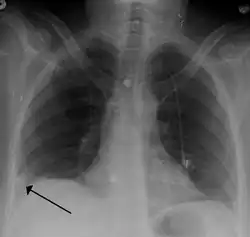

A Hampton hump in a person with a right lower lobe pulmonary embolism

To diagnose a pulmonary embolism, a review of clinical criteria to determine the need for testing is recommended.[34] In those who have low risk, age less than 50, heart rate less than 100 beats per minute, oxygen level more than 94% on room air, and no leg swelling, coughing up of blood, surgery or trauma in the last four weeks, previous blood clots, or estrogen use, further testing is not typically needed.[35]

• Chest X-rays are often done on people with shortness of breath to help rule out other causes, such as congestive heart failure and rib fracture. Chest X-rays in PE are rarely normal,[70] but usually lack signs that suggest the diagnosis of PE (for example, Westermark sign, Hampton's hump).